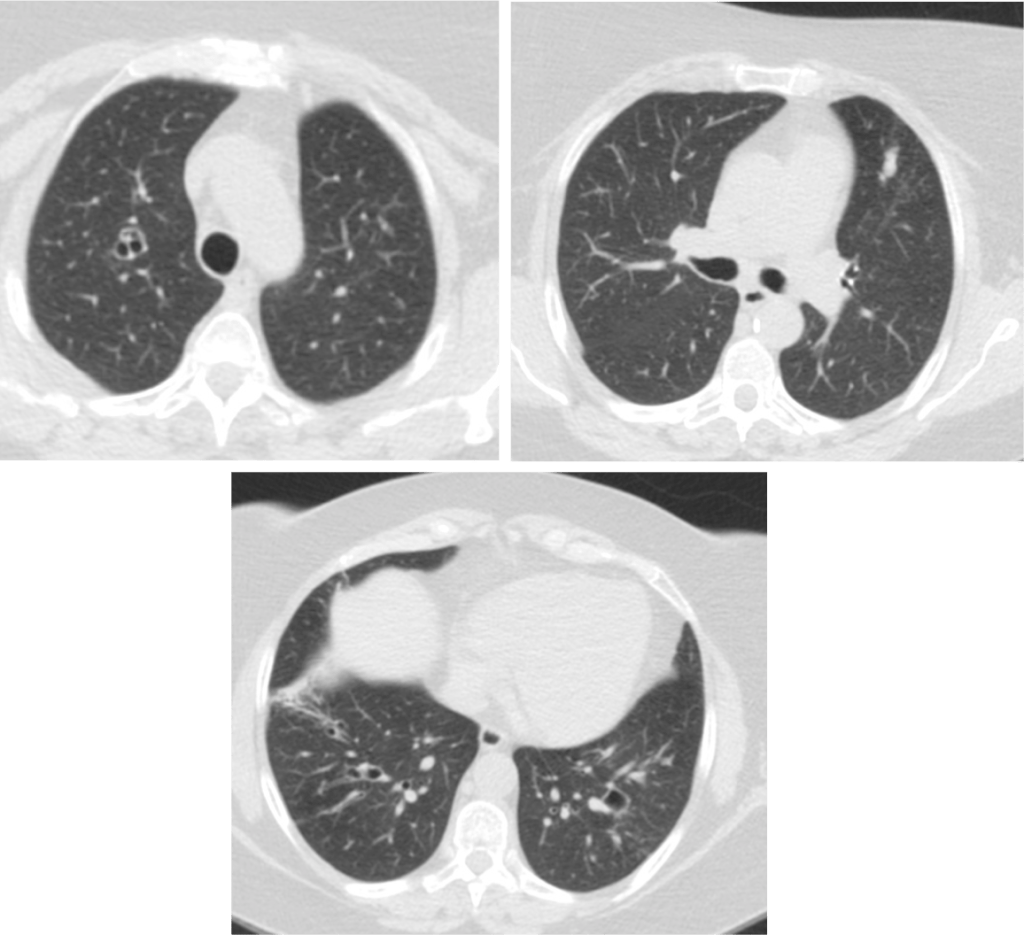

B). A. ALÉRGICA PULMONAR (ABPA):

Acontece en pacientes con asma, donde se produce una reacción de hipersensibilidad al aspergillus. La anatomía patológica se caracteriza por tapones mucosos con aspergillus y eosinófilos que se se acumulan en el interior de los bronquios produciendo dilataciones características de los bronquios segmentarios y subsegmentarios. Clinica: Dolor torácico, disnea, malestar general, fiebre, tos productiva, neumonías recurrentes.

Hallazgos radiológicos: Opacidades en dedo de guante en placa simple, Impactos mucoides en bronquios segmentarios y subsegmentarios sobre todo en lóbulos superiores en TAC, Atelectasias aisladas segmentarias, Bronquiectasias, Calcificaciones (30%). Hacer diagnóstico diferencial con otras etiologías como la atresia bronquial, lesiones bronquiales o bronquiectasias.

D). A. ANGIOINVASIVA:

Invasión de arterias de pequeño y mediano calibre por el aspergillus que formaran nódulos de necrosis o infartos hemorrágicos. Se da en pacientes inmunocoprometidos (SIDA), tasplantados, bajo tratamiento con quimioterapia, de difícil tratamiento como la leucemia resistente, linfoma, mieloma o bajo tratamiento con corticoides (enf, autoimunes) que padecen una neutropenia funcional.

Clinica: Fiebre + tos + disnea (ALTA mortalidad). Galactomanano +.

Hallazgos radiológicos: TAC, nódulos que pueden estar rodeados de halo de vidrio deslustrado (signo del halo). Estos hallazgos corresponden a infartos hemorrágicos (Diagnóstico diferencial: mucor, cándida, CMV, Hepres simple, Wegener, sarcoma de Kaposi, metástasis hemorrágicas. También puede haber «Signo de aire creciente» por necrosis de fragmentos hemorrágicos que se desprenden del parénquima sobre todo en el periodo de convalescencia.

E). A. INVASIVA DE LA VÍA AÉREA:

Aspergillus afectando la membrana basal de la vía aérea.

Clínica: Pacientes neutropénicos con traqueobronquitis, bronquiolitis, bronconeumonía.

Hallazgos radiológicos: La placa simple puede ser normal o presentar engrosamiento bronquial y traqueal. En el TAC: En la bronquiolitis, vemos microndódulos centrolobulillares con ramificaciones lineales dando patrón en árbol en brote de distribución parcheada (Diagnóstico diferencial con TBC, MAI, mycoplasma). En la bronconeumonía, consolidaciones peribronquiales (hallazgo inespecífico).